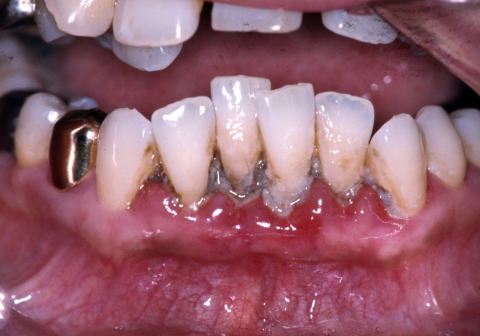

(図3)初診から2年後(1977年7月)、40歳。Splintせずに機能している

(図4)32年経過(2007年3月5日)、70歳。十分機能している